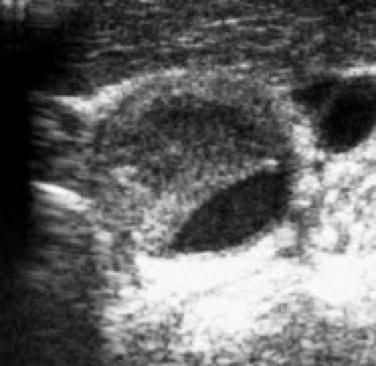

頚動脈狭窄病変のエコー写真(横断像)

頚動脈狭窄病変のエコー写真(縦断像)